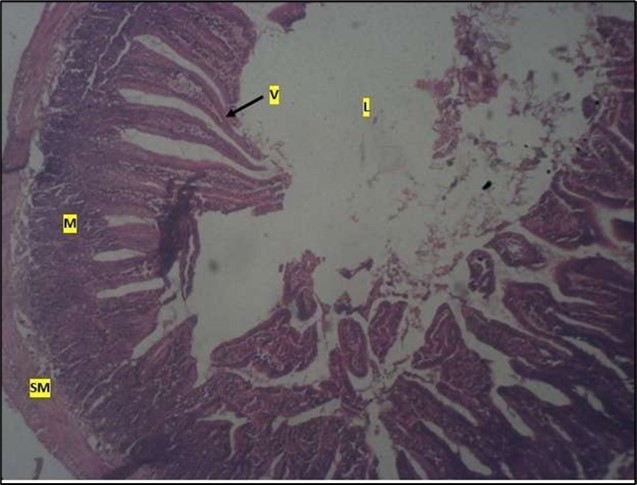

Micrographs of The Small Intestine

Histological examination of the small intestine result in control animals revealed a normal architecture with the red pulp and white pulp with no pathological observation Figure 2. Administration of Abelmoschus esculentus at low dose shows an increased cellularity with numerous cells in the Mucosa and the villi projecting towards the lumen. Focal metaplasia of mucosal cells alongside villous disruption was also observed (Figure 3). The high dose group showed normal cellular architecture with no villous disruption (Figure 4).

Figure 4.High dose showing a normal mucosa (m) with villi (v) projecting towards the lumen(l) and underlying smooth muscle layer (sm). No pathology seen